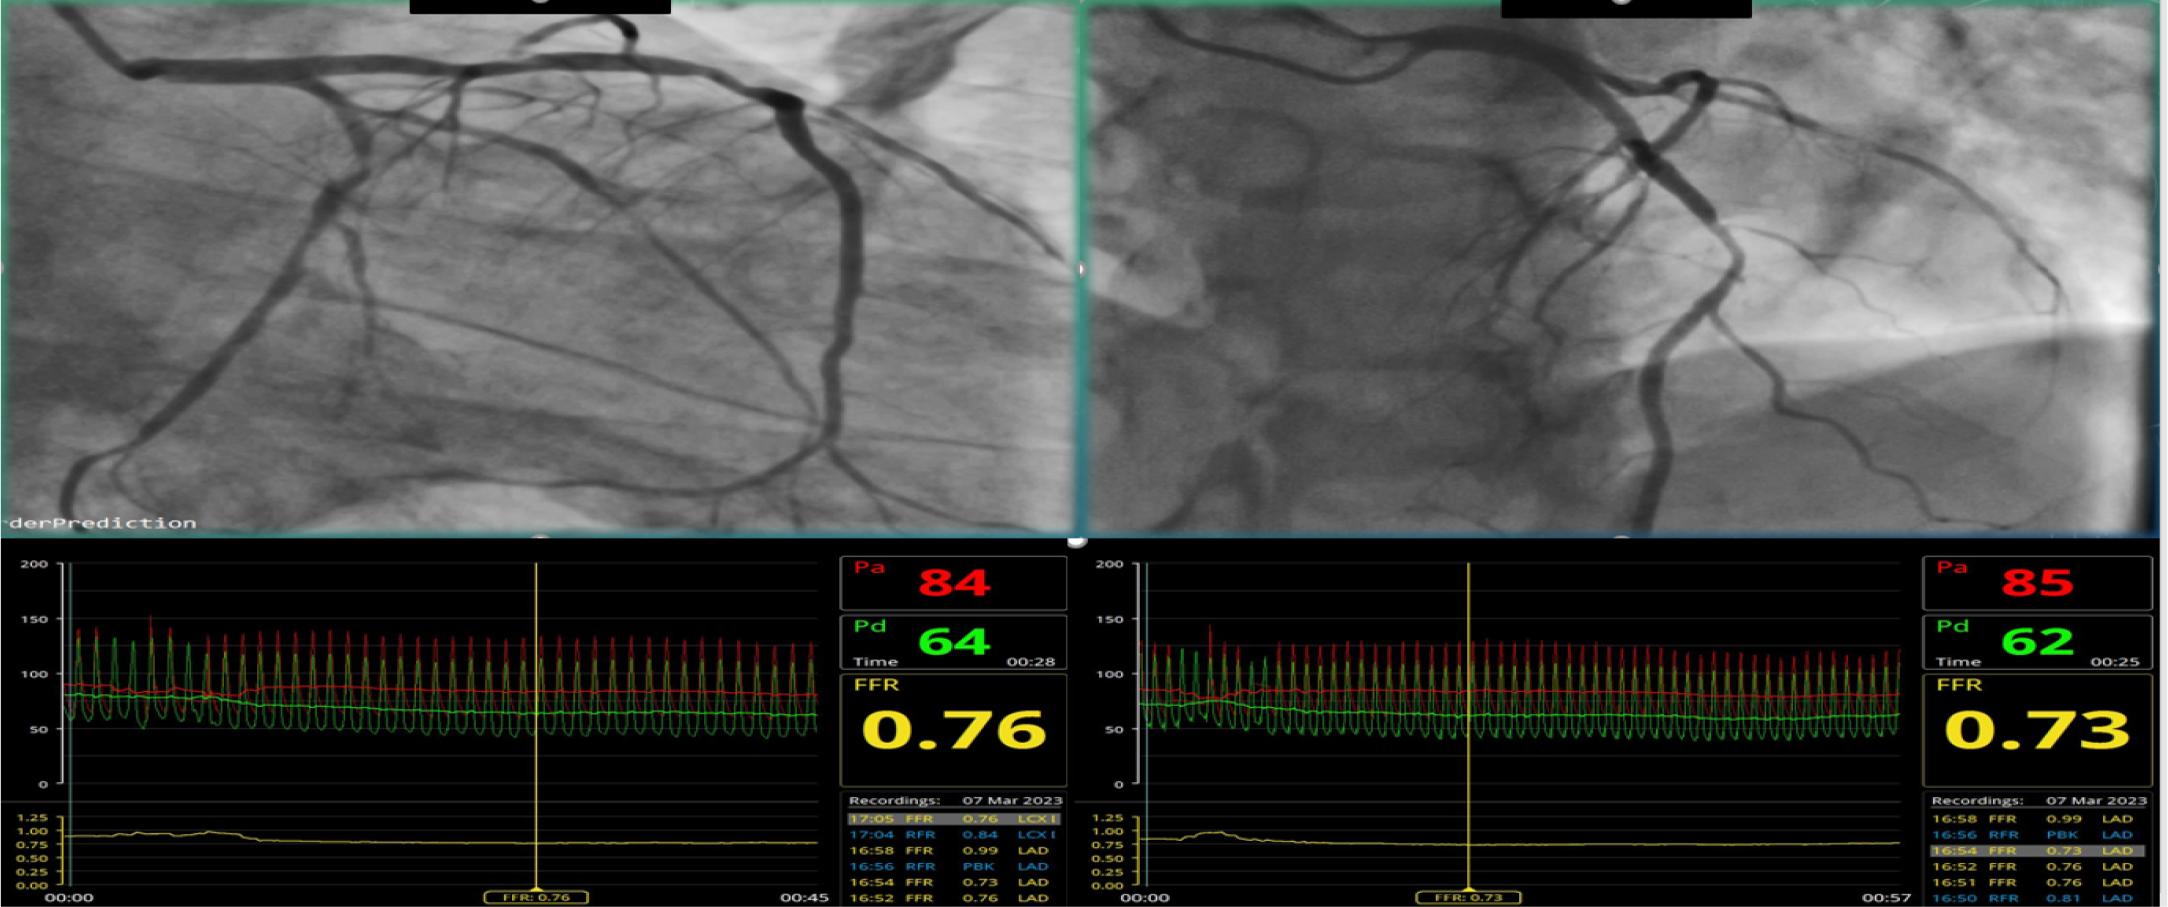

Figure 2A

Figure 2B